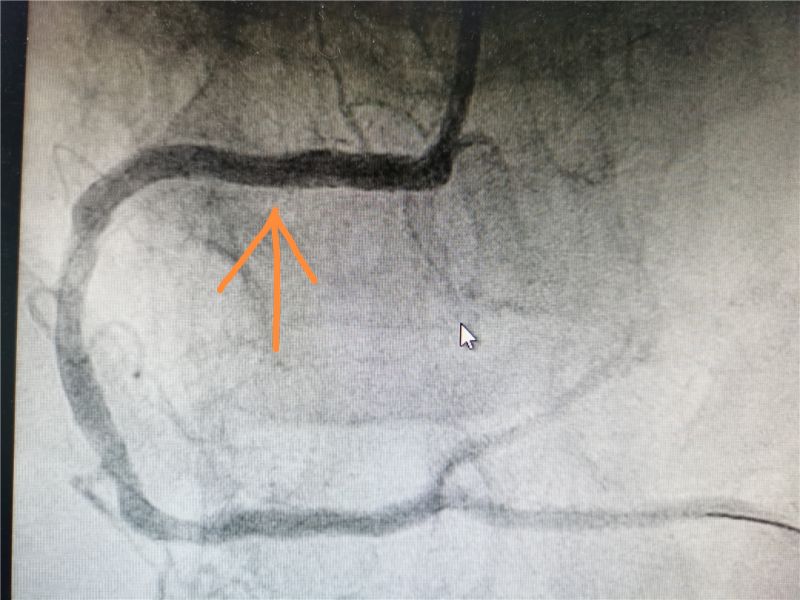

手术过程中,行冠脉造影可见患者右冠近端弥漫狭窄,最重95%,予以狭窄处植入一枚3.5mm*23mm可降解支架。可降解支架较目前主流的金属支架通过性差,较难通过病变,另外需要充分贴合血管壁避免支架内血栓的形成,因此在技术及经验等方面对术者要求较高。在宇大伟及其团队的精准实施和密切配合下,手术历时半个小时,患者冠状动脉血管恢复正常,无不良反应,手术圆满成功。

术后